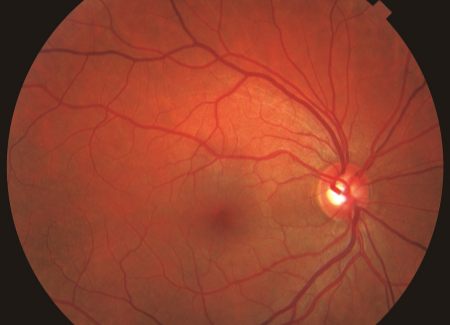

Learn moreDiabetic Eye Disease

The Diabetic Eye Disease Center of Excellence aims to advance available treatments for diabetic retinopathy. Researchers are studying risk factors for diabetes and diabetic retinopathy and evaluating novel approaches to therapy.